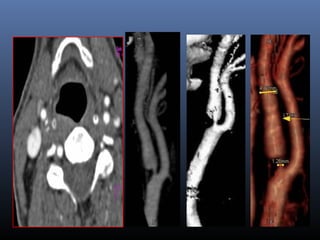

Dissection

 Imaging technique of choice

 MRA -2D TOF ,DSA-

Gradual irregular tapering,stenosis, Distal

emboli, psedoaneurysms

Non contrast fat supressed T1 sequence at base of skull and neck-

crescentic hyperintensity in vessel mura

CAROTID DISSECTION

VERTEBRAL ARTERY DISSECTION